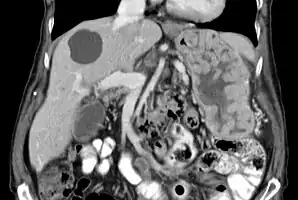

With Ménétrier disease, the stomach is characterized by large, tortuous gastric folds in the fundus and body, with the antrum generally spared, giving the mucosa a cobblestone or cerebriform (brain-like) appearance.[5] Histologically, the most characteristic feature is massive foveolar hyperplasia (hyperplasia of surface and glandular mucous cells).[3] The glands are elongated with a corkscrew-like appearance and cystic dilation is common. Inflammation is usually only modest, although some cases show marked intraepithelial lymphocytosis. Diffuse or patchy glandular atrophy, evident as hypoplasia of parietal and chief cells, is typical.[4]

The large folds of the stomach, as seen in Ménétrier disease, are easily detected by x-ray imaging following a barium meal or by endoscopic methods. Endoscopy with deep mucosal biopsy (and cytology) is required to establish the diagnosis and exclude other entities that may present similarly. A non-diagnostic biopsy may lead to a surgically obtained full-thickness biopsy to exclude malignancy.[3] CMV and helicobacter pylori serology should be a part of the evaluation.